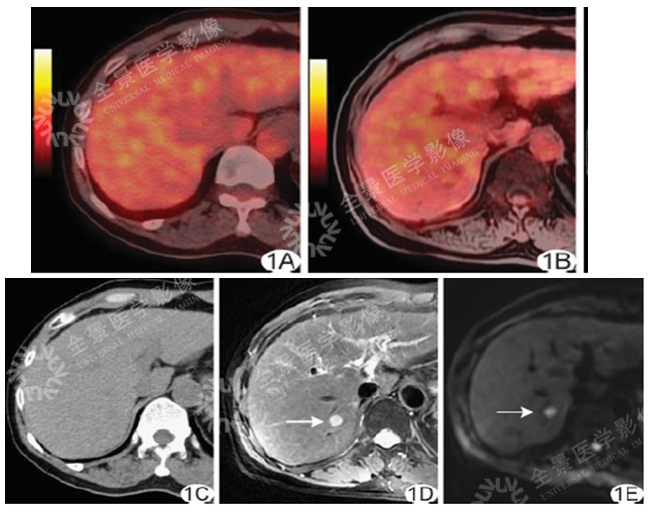

男 50岁 小肝癌:

案例一